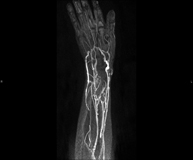

Angio-RM Lesió de parts tovesProva diagnòstica no invasiva que consisteix en l'estudi de la vascularització de qualsevol lesió de parts toves (com la pell, el músculs, els tendons, etc.) per obtenir imatges d'alta definició anatòmica mitjançant l'ús d'un camp electromagnètic i ones de ràdio (amb un emissor i un receptor). És indispensable l'ús de contrast intravenós paramagnètic (Gadolini). No obstant, no utilitza radiació ionitzant. La qualitat de les imatges permet realitzar reconstruccions en 2D i 3D. Està especialment indicat com a mapa vascular prequirúrgic en pacients amb lesions musculars, cutànies, subcutànies, etc.